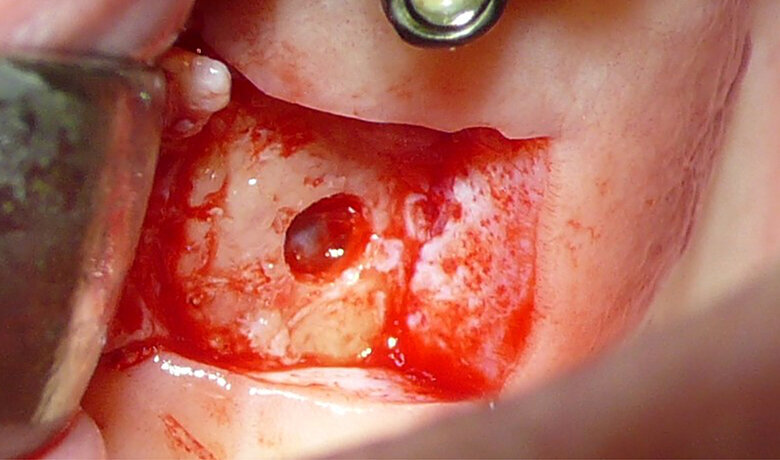

Figure 1 shows a split-mouth case with a bilateral INTRALIFT procedure: after a small crestal “booklet”-flap of approx. 7x7mm is detached, the sinus floor is safely opened with ultrasound Piezotome tips (Figs. 2 & 3), the sinus membrane then detached by the hydrodynamic cavitation effect of the Piezotome-tip TKW5 plugged into the approach canal (Figs. 4 & 5) and the subantral scaffold filled with 2cm of randomly assigned biomaterial (Figs. 6 & 7), followed by wound closure (Fig. 8). After a mean healing period of 8,4 months X-Mind trium CBCT scans were performed, the digital setup of the future bridge constructed with the AIS 3D app and the bone density determined in the sinus-lift site around a virtual implant (Fig. 9). Standardised implants (4mm in diameter and 12mm in length) were then inserted in the position of the virtual implant and insertion torque values (ITV) measured intra-surgically (test groups; Fig. 10). A total of 27 patients with sufficient native subantral crestal bone (min. crest width: 6 mm, height: 12 mm) were screened by X-Mind trium CBCT for bone density with the virtual implant (Fig. 11), the standardised implant inserted and the ITV recorded (control group). Figure 12 depicts the final result after implant insertion in the patient case shown in Figures 1–9.